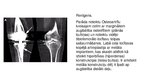

Osteoartrīts, arī osteoartroze ir locītavu slimības veids. Izraisa locītavu virsmu skrimšļu nodilumu un sekojošus bojājumus

Biežākie simptomi ir locītavu sāpes un stīvums. Sākumā tie var parādīties pēc fiziskām aktivitātēm, tomēr ar laiku simptomi var būt pastāvīgi. Vēl var būt locītavu pietūkums, ierobežota kustības spēja; gadījumos, kad tiek ietekmēta mugura, var būt roku un kāju vājums vai nejutīgums. Visbiežāk slimība skar pirkstu galu, īkšķa pamatnes, kakla, muguras, ceļgalu un gurnu

locītavas. Biežāk tiek skartas locītavas vienā ķermeņa pusē, nekā tās pašas otrā pusē. Problēmas parasti rodas gadu gaitā. Atšķirībā no citu veidu artrītiem, osteoartrīts parasti skar vienīgi locītavas.…